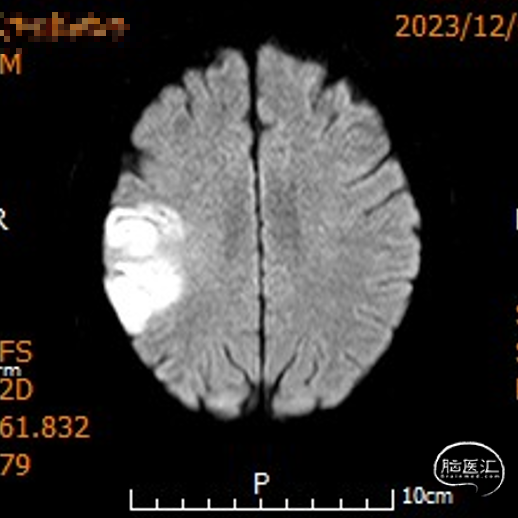

影像信息

颅脑CT示:

1.双侧侧脑室旁及右侧额顶叶多发脑梗死;

2.脑白质变性。

MRI示右侧颞顶叶及胼胝体急性脑梗死。